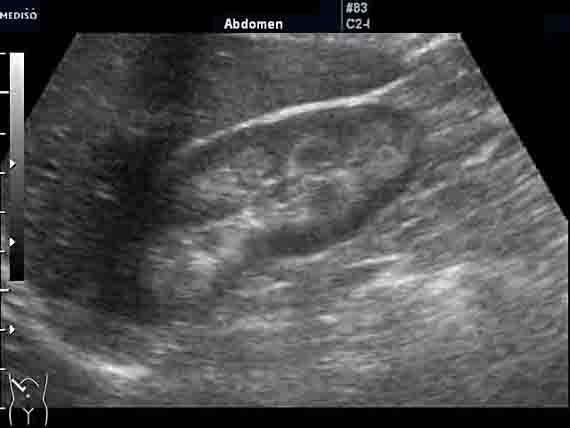

Женщина 50 лет. Прооперирована месяц назад по поводу альдостеромы левого надпочечника. Плановое УЗИ почек и надпочечников после операции. У нас смотрится впервые.

На УЗИ выявляю изменения в почках - см. фото. Паратгормон и уровень мочевой кислоты в норме. Креатинин 100-110. Меня старательно уверяют, что почки нормальные. И на МРТ, сделанной перед операцией, почки были якобы не изменены (но снимки потеряли). Отправил пациентку за копией снимков (в "живом" или цифровом варианте). Но большой надежды на восстановление данных нет.

Как вам кажется, коллеги: это нормальные почки? Я не исключаю в т.ч. и один из вариантов "губчатой почки".

Правая почка.

Сонографическая картина нефрокальциноза. В некоторых пособиях такую картину называют "почками Андерссон-Карра".